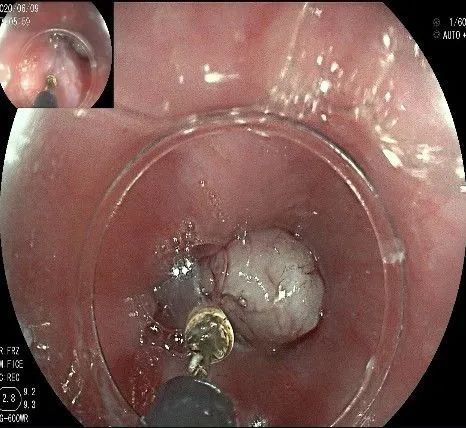

倒镜观察,可见贲门部一个明显的隆起,中央部分的凹陷,是4天前取活检留下的。

我们的思路:病变长径约2.0cm,位置活动,倒镜后先在胃底侧粘膜下注射,使病变向食管腔方向抬举,然后再在食管腔内做粘膜下注射切开,以获得一个好的术野,果然,注射后粘膜抬举明显,瘤体被挤向口侧。

在食管腔内,瘤体的两侧行粘膜下注射后,在瘤体顶部纵向自口侧向肛侧切开食管粘膜。